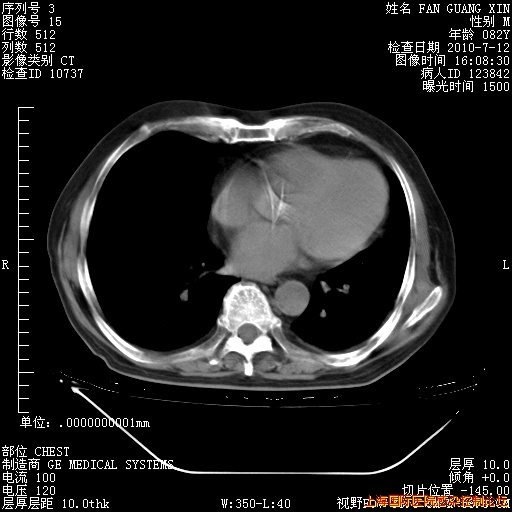

今天CT

整整相隔30天的肺部CT好像有所好转啊。甲强龙减量第3天,需要观察体温。